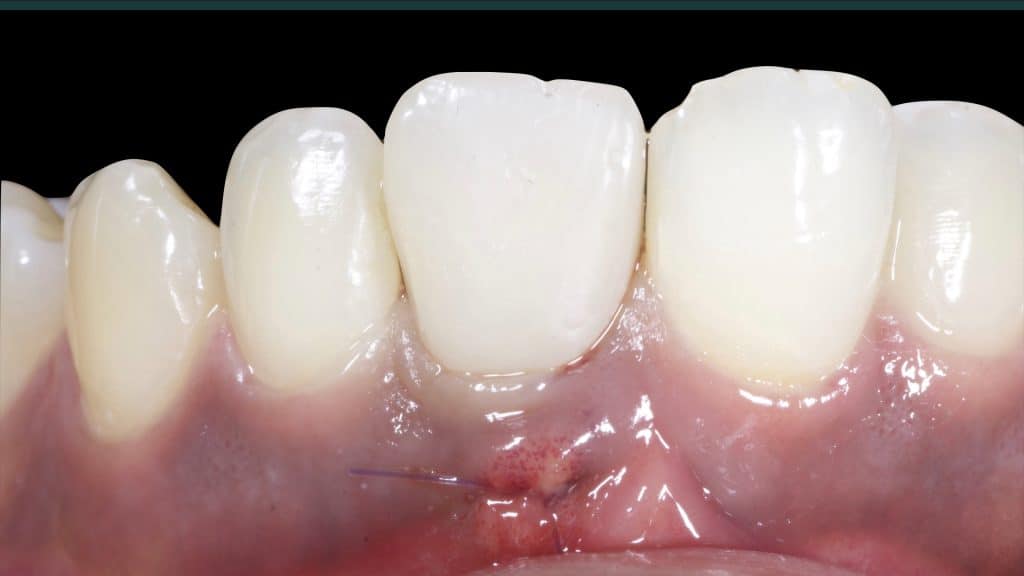

Immediate post-op

20 days post-op after suture removal